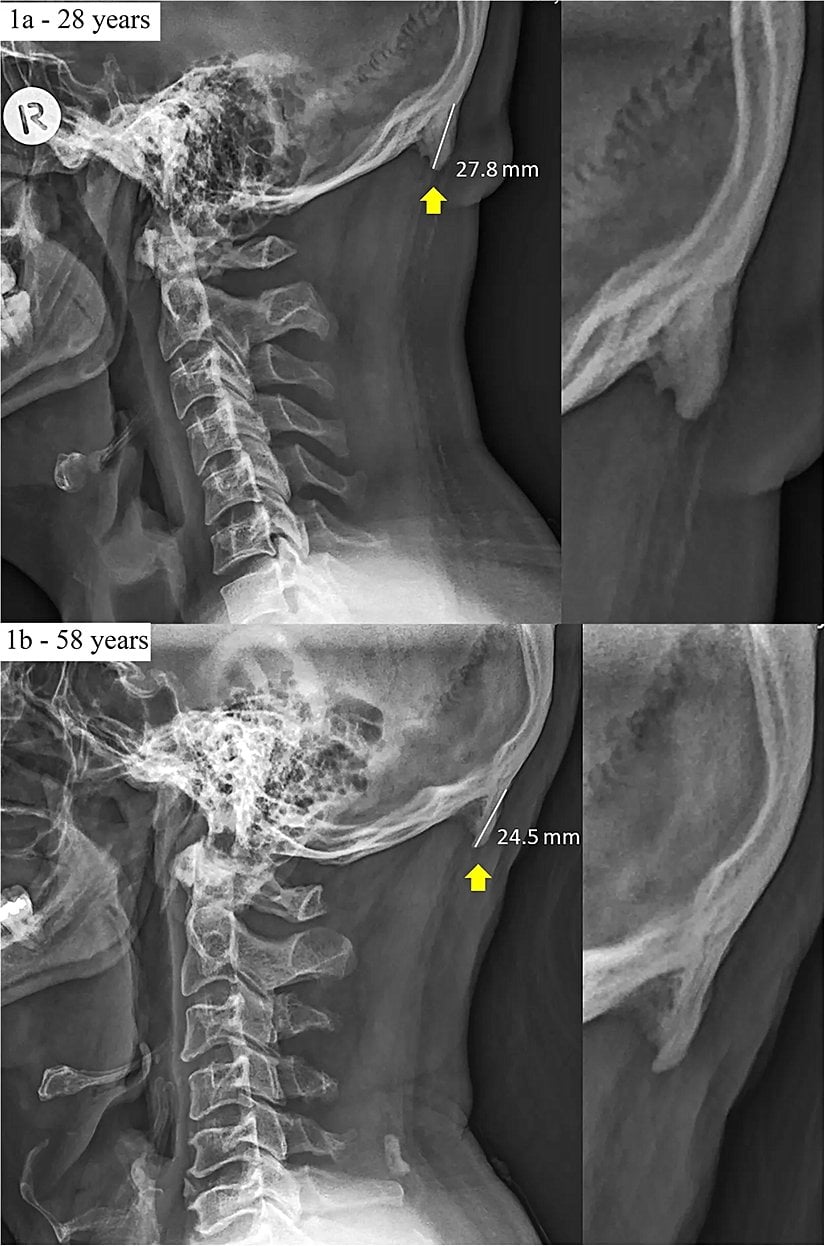

Söz konusu kemik uzantısını ortaya çıkaran veriler, 3 yıldır boyunca Avustralya'nın Queensland bölgesinde çekilen X-ışını taramalarından geliyor. Bu taramalarda, söz konusu çıkıntıların da bulunduğu bölgenin fotoğrafları çekildi. Normalde bu kemik uzantıları çok şaşırtıcı değil ve yaşlılarda görülüyor; çünkü yıllar yılı hayatta kalıp, boyun kaslarına yük bindirince, bu kemikler de ilerleyen yaşlarda gelişebiliyor. Ancak şaşırtıcı olan, genç yetişkinlerde de bu kemiklerin gözükmeye başlamış olması. Hem de kimi zaman bu genç yetişkinlerde yaşlılardan bile daha uzun kemikler görülüyor!

Aynı araştırmacılar, 2016 yılında Journal of Anatomy dergisinde yayınladıkları makalede, 18-30 yaş arası 218 kişiye ait X-ışını taraması fotoğrafını analiz ederek bu kemik büyümesinin genç yetişkinlerin %41'inde görüldüğünü tespit etmişlerdi. Bu kemikler, erkeklerde kadınlara göre daha belirgindi.

Genişlemiş dış oksipital çıkıklık (İng: external occipital protuberance) adı verilen bu durum eskiden gençlerde çok nadiren görülmekteydi. Ancak 2018 yılında Clinical Biomechanics dergisinde yayımlanan bir çalışma, bunun gençlerde daha sık görülmeye başlandığını ve sebebinin genetik veya enflamasyon gibi faktörler olmadığını; daha ziyade mekanik yük binmesi sonucu olduğunu gösterdi.

İşte bundan yola çıkan araştırmacılar, nihayetinde 18-86 yaş arası insanlara ait 1200 X-ışını taramasını inceleyerek, bu kemiklerin popülasyonun %33'ünde bulunduğunu ve şaşırtıcı bir şekilde artık yaş ilerledikçe bu kemiklerin kısaldığını gösterdiler! Bu keşif, yerleşik bilimsel bilgilerimizle fazlasıyla zıt. Çünkü normalde bu çıkıntılı kemiklerin ilerleyen yaşlarda daha da uzadığı düşünülmekteydi! Shahar şöyle diyor:

Biyomekanik alanında çalışmalar yürüten uzmanlar söz konusu kemik çıkıntısı uzamasının özellikle gençlerde daha sık ve daha belirgin olmasının ana sorumlusunun telefona bakmak için öne eğilen kafaların yarattığı kütle merkezi değişiminin kafataslarında boynuz-benzeri uzantıların gelişmesine neden olduğunu düşünüyorlar. Kafamızı durmaksızın öne eğince, kafamızın ağırlığını dengeleyen kas grupları, omuriliğimiz hizasından kafanın arkasındaki kaslara doğru kaymaktadır. Bu da, bu yeni pozisyonda yeni kemik, tendon ve ligament gelişimini pekiştirmektedir. Bu da, boynun hemen üzerinde boynuz-benzeri kemiklerin belirmesi anlamına gelmektedir.